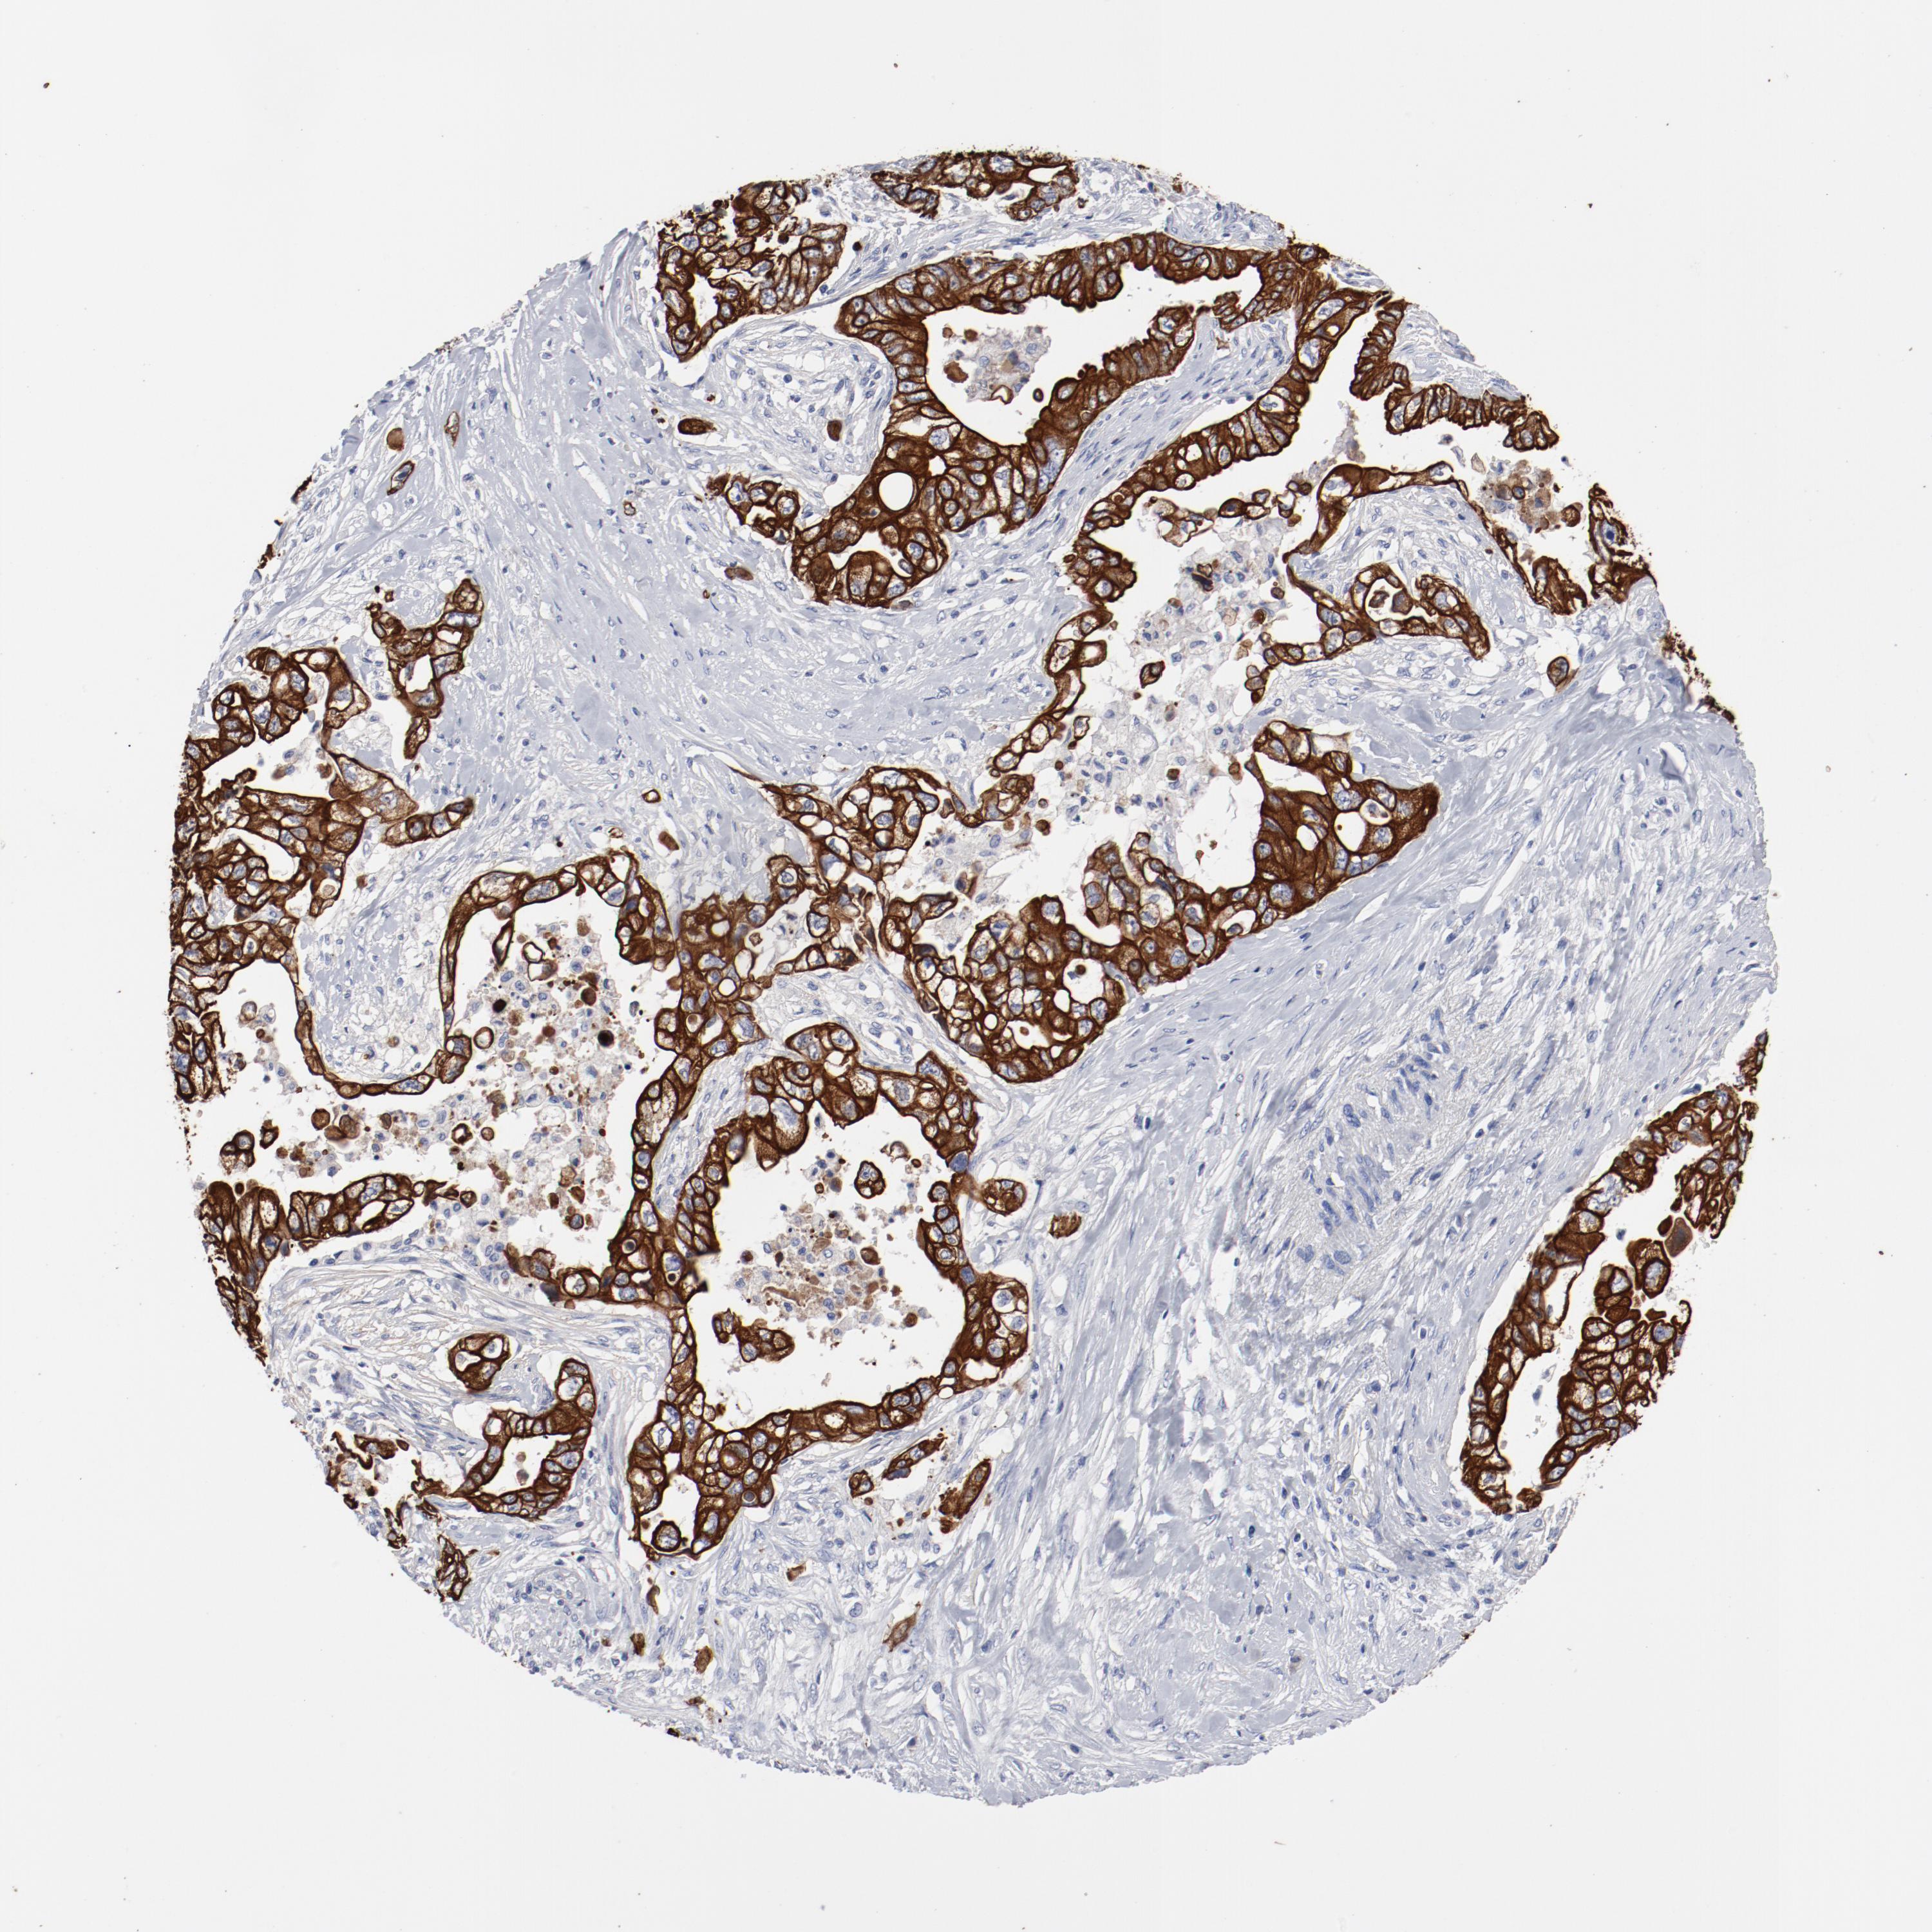

PANCREATIC CANCER - Protein expressioni

A mouse-over function shows sample information and annotation data. Click on an image to view it in a full screen mode. Samples can be filtered based on level of antibody staining by selecting one or several of the following categories: high, medium, low and not detected. The assay and annotation is described here.

Note that samples used for immunohistochemistry by the Human Protein Atlas do not correspond to samples in the TCGA dataset.

Antibody stainingi

Antibody staining in the annotated cell types in the current human tissue is reported as not detected, low, medium, or high, based on conventional immunohistochemistry profiling in selected tissues. This score is based on the combination of the staining intensity and fraction of stained cells.

Each image is clickable and will lead to virtual microscopy that enables deeper exploration of all samples and also displays staining intensity scores, fraction scores and subcellular localization as well as patient and tissue information for each sample.

Antibody HPA004109

Staining

High

Medium

Low

Not detected

Intensity

Strong

Moderate

Weak

Negative

Quantity

>75%

75%-25%

<25%

None

Location

Nuclear

Cytoplasmic/membranous

Cytoplasmic/membranous,nuclear

Adenocarcinoma, NOS

Adenocarcinoma, metastatic, NOS